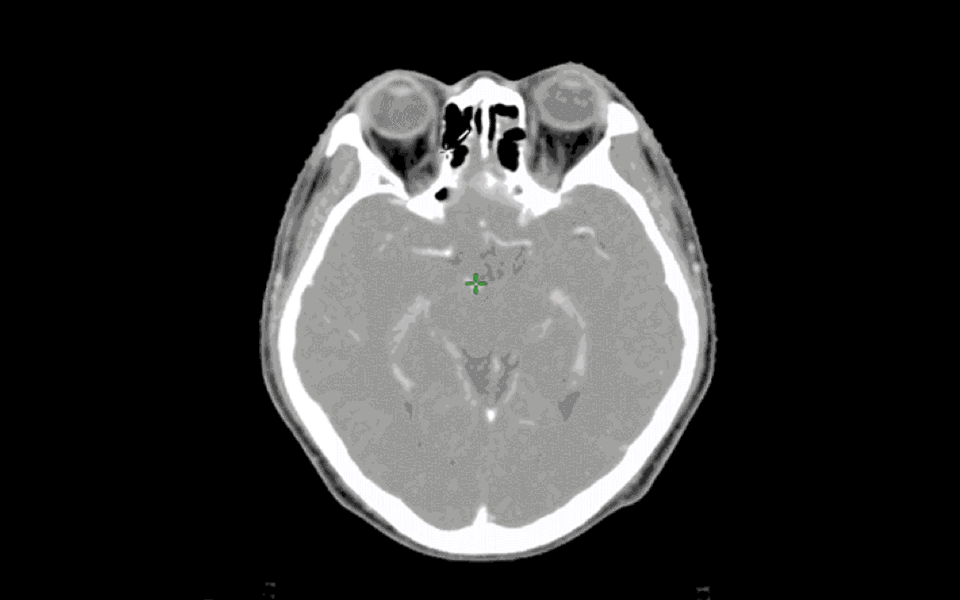

RAIC·OIS是(shi)基(ji)于放(fang)(fang)射治療(liao)(liao)的標準流程(cheng)(cheng),結合人工(gong)智(zhi)(zhi)能(neng)(neng)技術開發的放(fang)(fang)療(liao)(liao)管理平臺(tai)。具有患者電子病歷管理,患者治療(liao)(liao)流程(cheng)(cheng)跟蹤,放(fang)(fang)療(liao)(liao)影像智(zhi)(zhi)能(neng)(neng)勾靶(ba)三大功能(neng)(neng),全面支持(chi)Dicom服務協議,與放(fang)(fang)療(liao)(liao)設備互(hu)(hu)聯互(hu)(hu)通(tong),直擊放(fang)(fang)療(liao)(liao)痛點(dian),極大的提(ti)高了放(fang)(fang)療(liao)(liao)工(gong)作(zuo)效率。

利用大數據、機器學習(xi),實(shi)現智能器官勾畫,提高放療工作(zuo)人(ren)員的工作(zuo)效(xiao)率與工作(zuo)質量(liang),降(jiang)低出錯概率